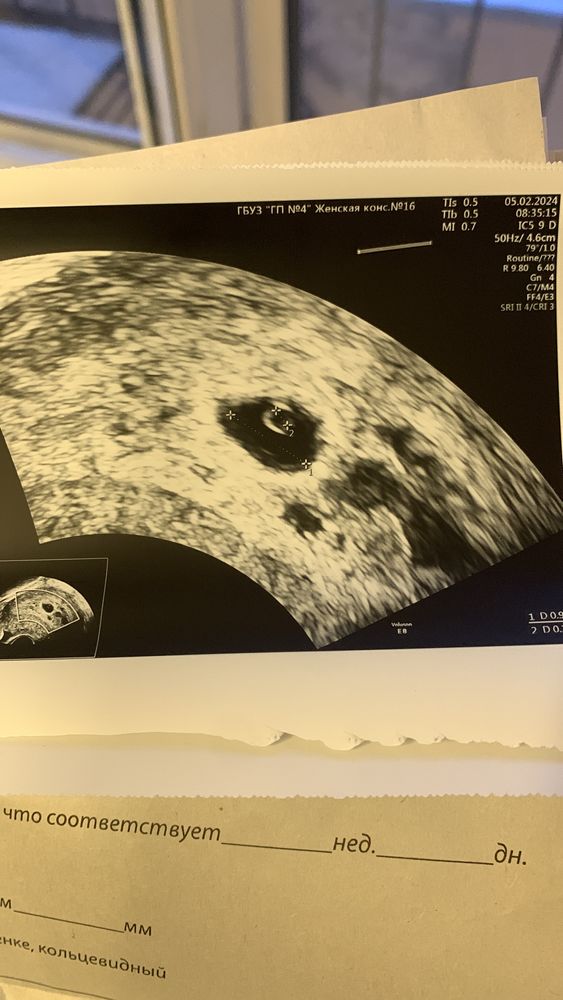

Mura, для сердечка еще рано , через 2 недели пойду слушать его 🥰 у меня овуляция была 10 января🥰 цикл длинный , обычно 32 дня и по м. Срок сегодня 6 недель, но по овуляции 5 и 4🥰 так что сегодня должны увидеть пя🥰 и мешочек 🥰

Sunny girl , да вроде) жм 2,2 мм, лялька есть, но совсем крошечный, сказали через 2 недели приходить)